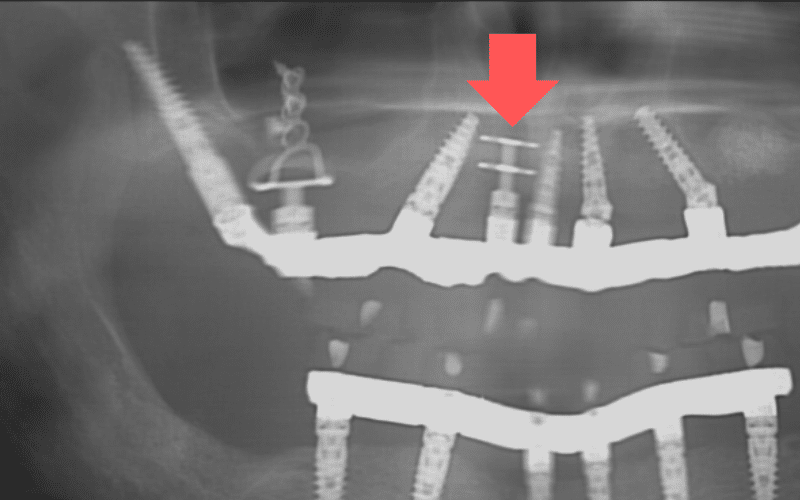

שתלי דיסק, הידועים גם כשתלי BOI (Basal Osseo-Integrated) או שתלי צלחת (Plate-Form Implants), הם סוג של שתלים שפותחו במיוחד למטופלים עם חוסר עצם משמעותי.

המבנה הייחודי

שתלי דיסק מאופיינים בצורתם הייחודית הכוללת:

עקרון הפעולה

בניגוד לשתלים רגילים המוחדרים אנכית לעצם, שתלי דיסק מוחדרים לרוחב העצם ומעוגנים בשכבת העצם הקורטיקלית החזקה משני צדי הלסת. זה מאפשר עיגון חזק גם במקרים של עצם דקה מאוד.